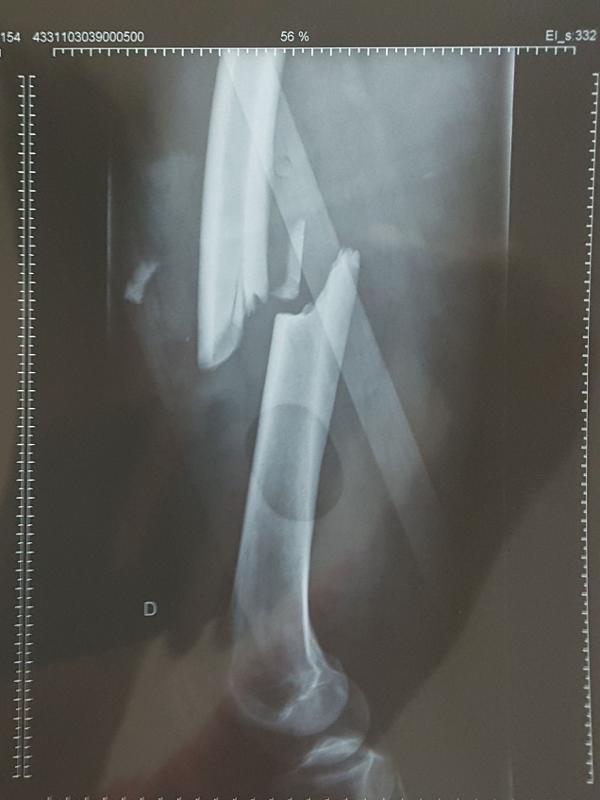

Fui girando na pista e dei na barreira de pneus na posição de leg press de academia. A energia da batida foi subindo e afetando tornozelo, joelho, quadril. Essa energia fez meu fêmur dobrar igual a um canudo. O osso subiu e rasgou meu macacão.

Os médicos falaram que não teve massagem. Deram injeção de adrenalina. Aí me levaram para o ambulatório. Fratura exposta de fêmur. É grande a bitola do osso, um troço absurdo. Cortaram meu macacão e o sangue jorrava tanto que os caras limpavam com rodo.

Só me botaram na ambulância quando comecei a dar sinais de vida. A pupila dizia que o cérebro funcionava, mas eu mesmo não lembro de nada. Meu capacete estava todo marcado e fui para tomografia. Havia um coágulo no cérebro. Botaram a gaiola no fêmur e deixaram a perna parada. Primeiro cuidariam da cabeça.

Eu tinha lampejos, segundos de consciência e apagava. Só fui ver que tinha um monte de fios enfiados em mim no dia em que foram tirados porque eu estava deixando a UTI. Saí de lá com uma placa de titânio que vem da cabeça do fêmur até o joelho. Dois parafusos em cima, dois embaixo.